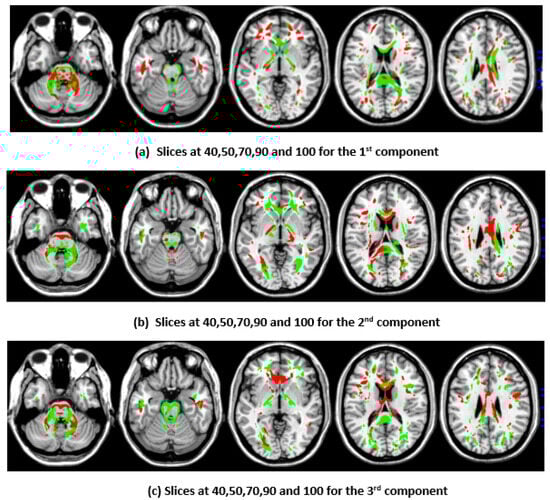

3.4. Top Brain Regions Contributing to CCA and DCCAE Components

To illustrate the brain regions, the top PCs of the first three significantly correlated GM and FA components were plotted for both the CCA results and the DCCAE results. To plot the brain regions, the CCA/DCCAE components were traced back to PCA components using the weight matrix of CCA/DCCAE, and the top PCA components were then mapped to the brain regions.

Figure 1 and Figure 2 depict GM and FA regions for CCA, respectively, while Figure 3 and Figure 4 portray GM and FA regions for DCCAE, respectively, with green indicating positively correlated GM and FA regions and red indicating negatively correlated regions. The GM regions identified via the first component of CCA with their respective volume in cubic centimeters (cc) include the middle temporal gyrus (12.1 cc), pre-central gyrus (14.5 cc), middle frontal gyrus (14.6 cc), superior frontal gyrus (2.0 cc), and sub-gyral regions (12.7 cc). The second component highlights the cuneus (27.3 cc), middle occipital gyrus (10.6 cc), superior frontal gyrus (6.3 cc), lingual gyrus (13.4 cc), and superior temporal gyrus (8.4 cc). The third component encompasses the superior frontal gyrus (27.2 cc), middle frontal gyrus (12.6), cuneus (23.6), superior temporal gyrus (10.8), middle occipitalgyrus (16.0 cc), and thalamus (17.4 cc). Similarly, the first component of DCCAE reveals Cuneus (15.4 cc), middle temporal gyrus (22.1 cc), precentral gyrus (15.6 cc), middle frontal gyrus (20.1 cc), superior temporal gyrus (6.8 cc), inferior parietal lobule (17.3 cc), and superior frontal gyrus (29.2 cc). The second component identifies cuneus (19.6 cc), middle occipital gyrus (11.1 cc), superior frontal gyrus (30.4 cc), middle frontal gyrus (20.1 cc), sub-gyral (9.1 cc), postcentral gyrus (9.5 cc), precuneus (6.0 cc), and middle temporal gyrus (10.3 cc). The third component includes the middle temporal gyrus (23.7 cc), precentral gyrus (11.0 cc), cuneus (29.0 cc), lingual gyrus (6.3 cc), middle occipital gyrus (14.3 cc), inferior frontal gyrus (2.3 cc), postcentral gyrus (10.8 cc), and inferior parietal lobule (6.8 cc).

When examining the direct similarity between components of CCA and DCCAE, we found that most of the CCA components (for both GM and FA) have high and significant correlations (shown in Table 3 and Table 4) with some of the DCCAE components. For example, CCA GM component first is significantly and negatively correlated to DCCAE GM components first and second, and it is positively correlated to DCCAE GM component third. Similar results were observed for FA components; CCA FA component first was linked to DCCAE FA components first and second negatively and component third positively. The negative correlation observed in Table 3 and Table 4 does not indicate a fundamental contradiction in the relationship between GM and FA features. Instead, it suggests that, for the same brain region, CCA encodes a change in one direction (an increase or a decrease), while DCCAE encodes it in the opposite direction. However, the underlying GM-FA association remains consistent across both models. This difference in sign can be further illustrated in Figure 1 and Figure 3, where the first components from CCA and DCCAE show similar spatial patterns, particularly in the posterior occipital region, but the color representation differs, indicating an increase in one model and a decrease in the other.

Figure 1. First, second, and third components of GM identified through CCA.